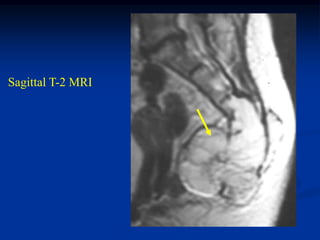

Sagittal T-2 MRI